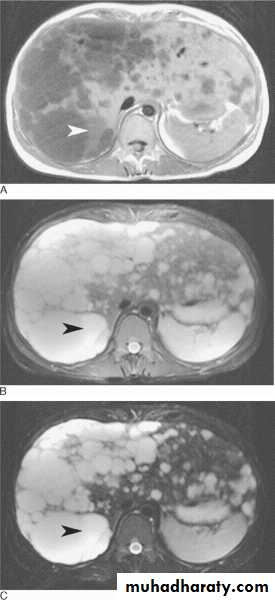

The most widly used agents are gadolinium compounds which only cross the B.B.B. when it is damaged by disease and which concentrate in tissue and diseases processes with high blood supply .

Tissue which concentrate the agent show very high intensity ( they appear white ) on T1 –images .Tissue specific media ,such as iron oxide agents for reticuloendothelial cells imaging .